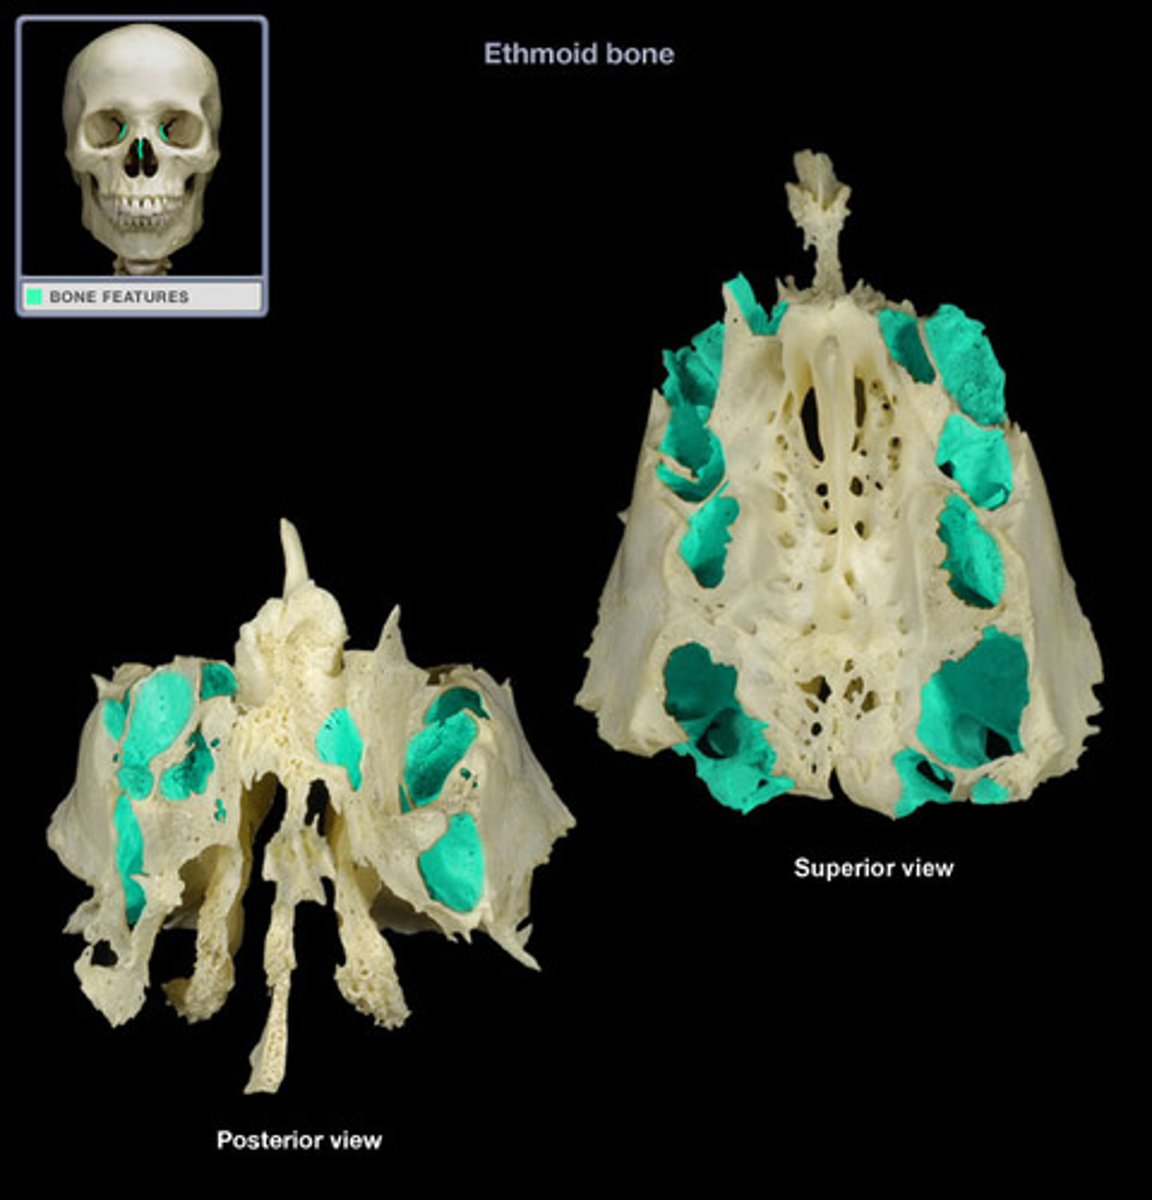

Anatomy- Ethmoid Bone

Crista galli

Vertical projection of the ethmoid bone.

Cribriform plate

Horizontal bone structure with olfactory foramina.

Body

Central part of the ethmoid bone.

Orbital plate

Lateral surface forming part of the orbit.

Lacrimal papyracea

Thin plate of bone in the eye socket.

Anterior ethmoid foramen

Opening for nerves and vessels at the front.

Posterior ethmoid foramen

Opening for nerves and vessels at the back.

Ethmoid air cells

Air-filled spaces within the ethmoid bone.